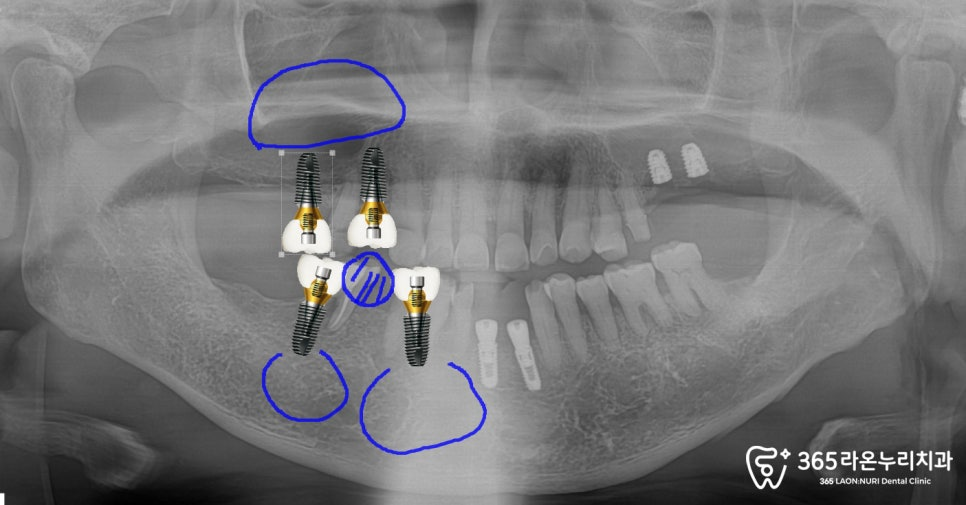

오른쪽 위 아래 턱 동그라미 친 부위에

심으면서 뼈이식을 함께 진행하려는

계획에 대해, 환자께 자세히

설명을 드렸던 흔적입니다. ^^

그리고, 오른쪽을 보시면 흔들리던

어금니가 사라지고 임플란트

수술을 통해 새로운

픽스처가 자리를 잡았습니다.

픽스처가 흔들리지 않게,

뼈이식 과정을 통해

튼튼하게 고정될 수 있게끔

만들어드렸습니다.

그렇게 유착되기를 기다리면서

오른쪽 위 아래 모두 어버트먼트+임시 치아를

올려드린 모습입니다.